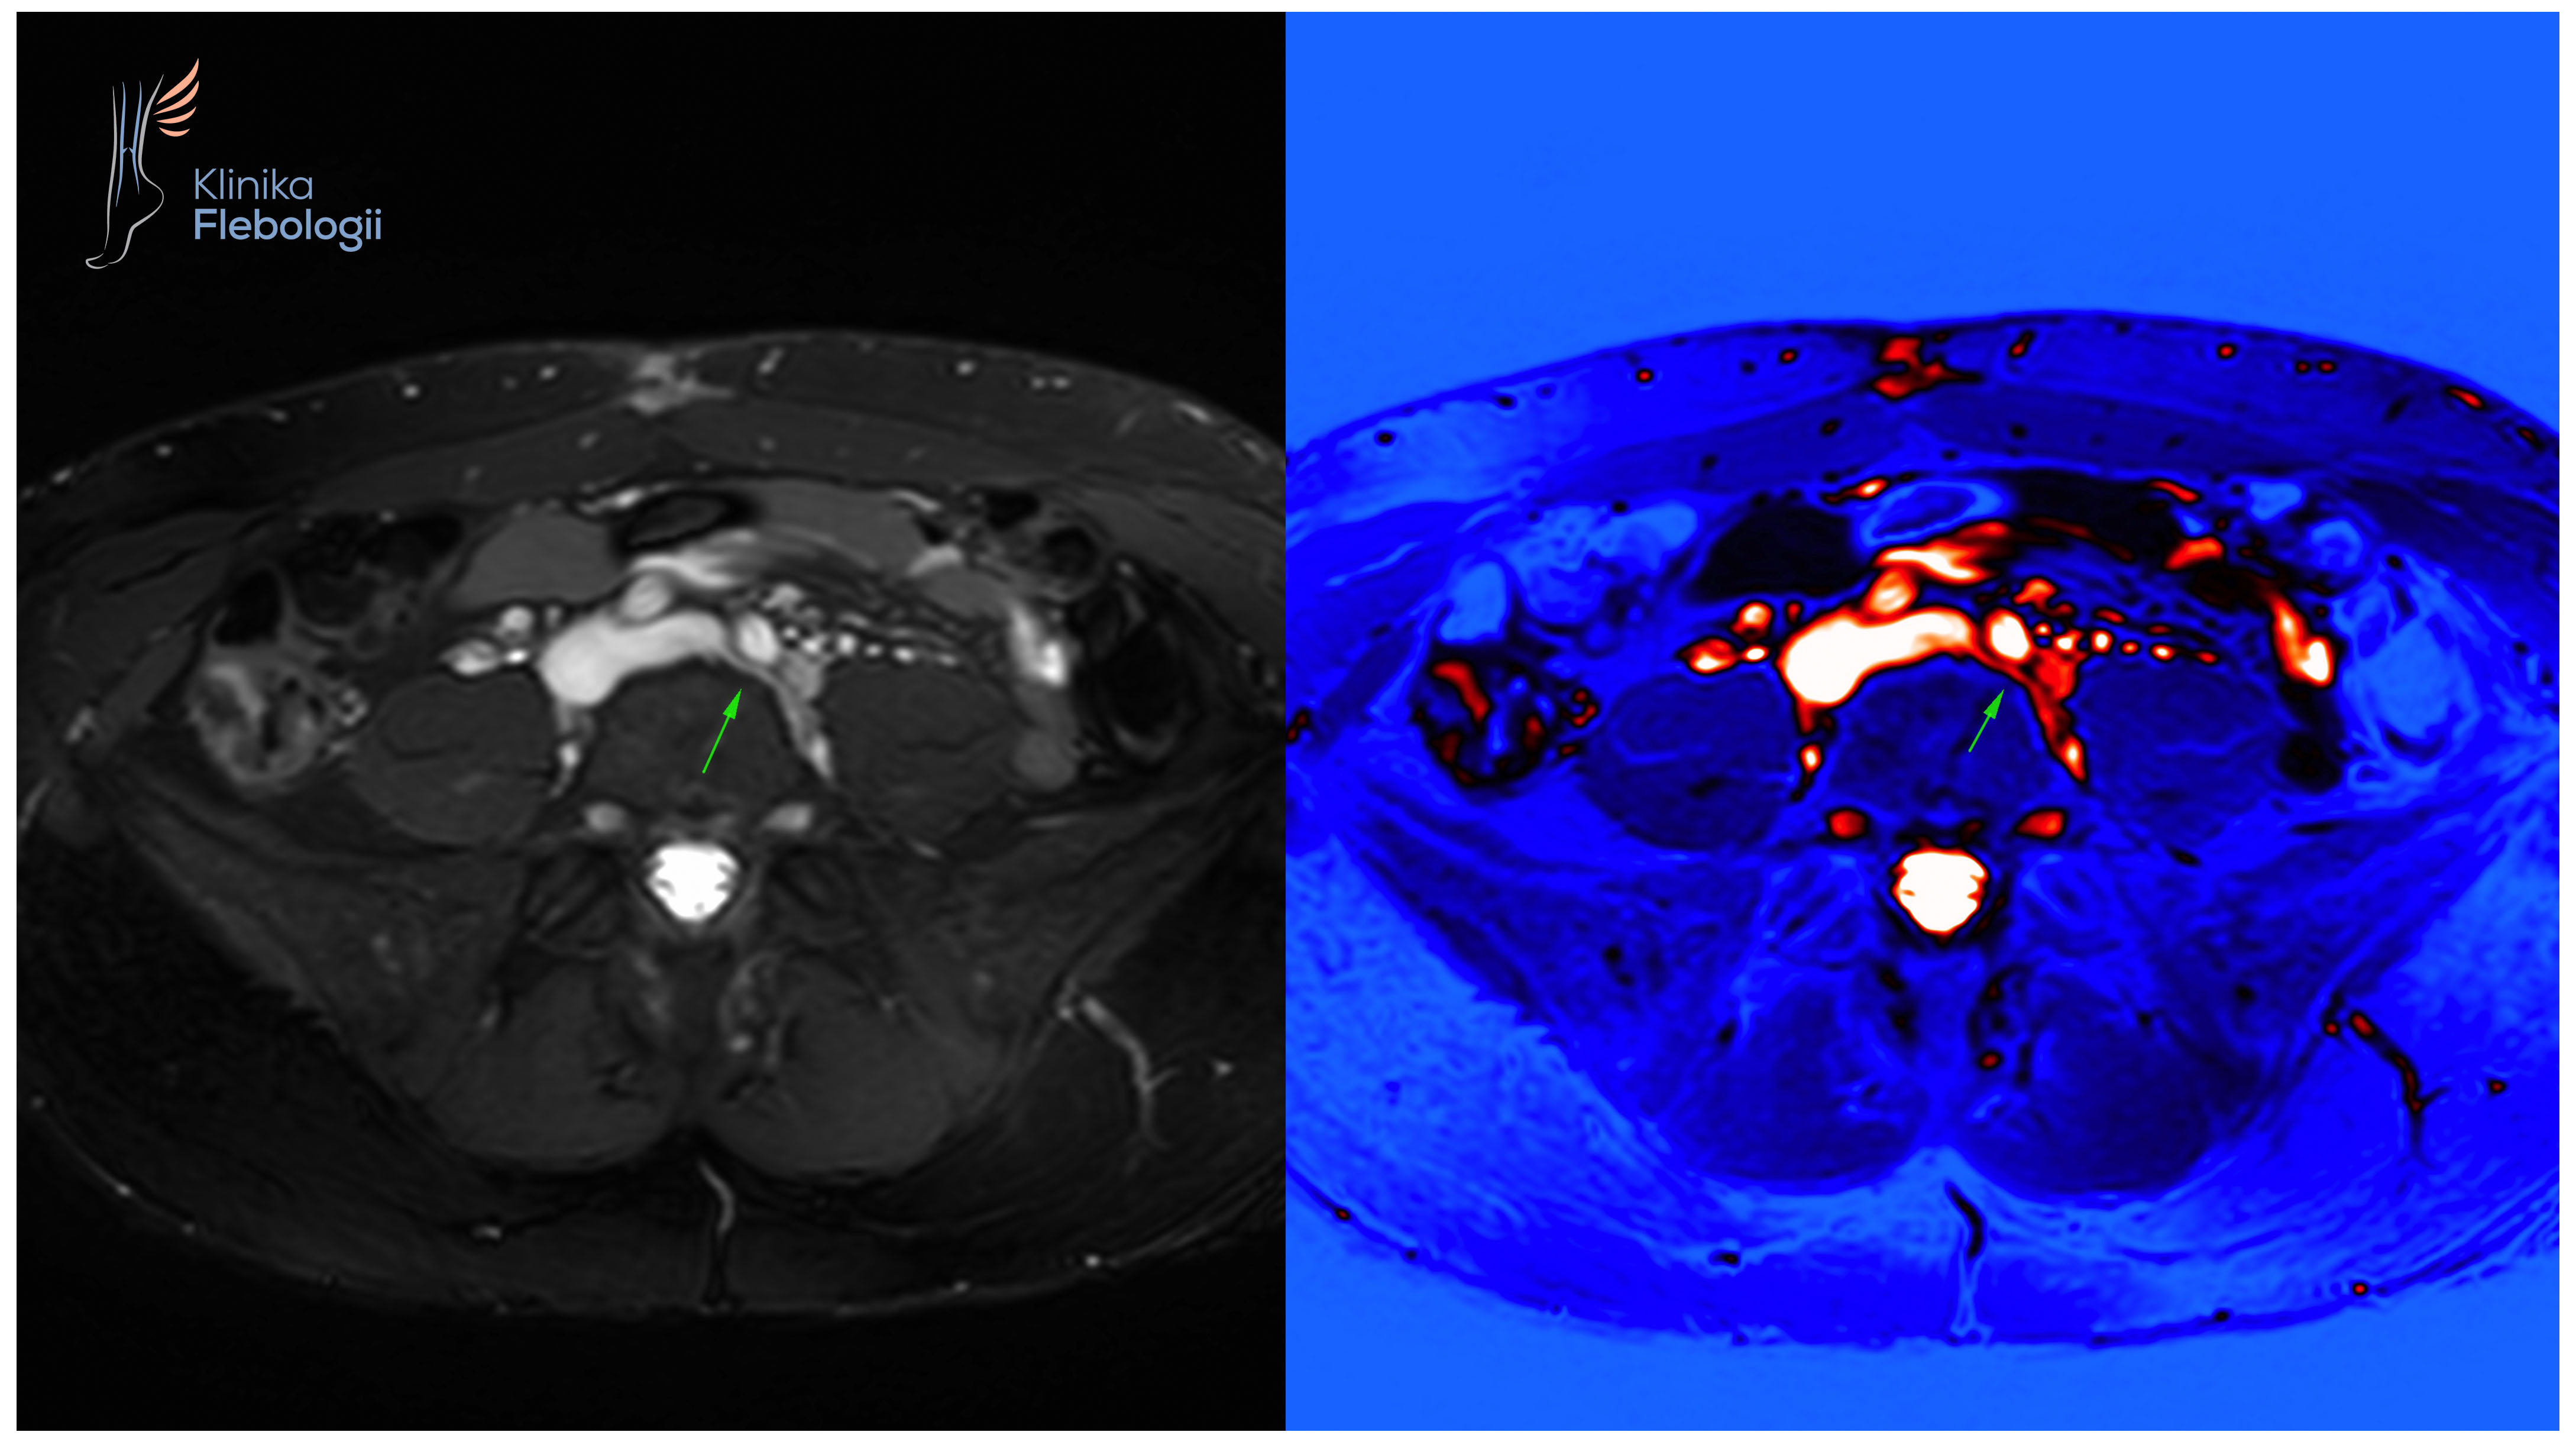

Rzadka postać żylnego zespołu uciskowego na poziomie spływu lewej żyły biodrowej wspólnej.